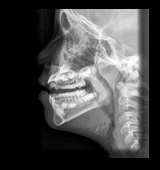

Radiografía lateral de un paciente con agrandamiento de amígdalas y adenoides • Imagen • MEDtube.es